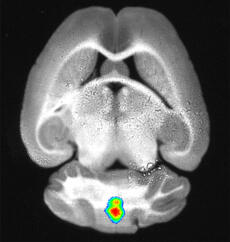

Inflammation in a mouse’s brain (fluorescence reflectance imaging).

© Hanna Gerwien, Andreas Faust, Lydia Sorokin, Michael Schäfers

To make the tiny structures in a mouse’s brain visible, the chemists linked the MMP tracer to a fluorescent tag. The fluorescence light signal from such a tracer can be measured using optical imaging techniques. Dr. Hanna Gerwien, who has just completed her PhD in biology, injected the tracer into diseased mice and examined the animals using fluorescence ­reflectance imaging. This technique visualizes the fluorescent tracers in the near-infrared range in a living organism. The researchers discovered that the tracer accumulated in high ­concentrations in certain parts of the brain.

To investigate whether the tracer signal correlated with MMP activity at the blood-brain barrier and with immune cell infiltration, Hanna Gerwien removed the brain and examined it under the microscope. The result was that the localization of MMP activity and immune cells matched the fluorescence tracer signal. “We found that our observations of MMP activity provided precise information on where the immune cells penetrate the blood-brain barrier and where inflammation occurs in the brain,” says Hanna Gerwien.